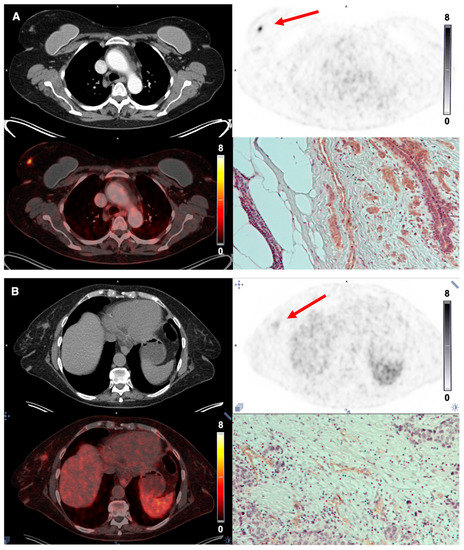

3.5. Tumor Uptake of [68Ga]Ga-NODAGA-E[c(RGDyK)]2 and Target Validation